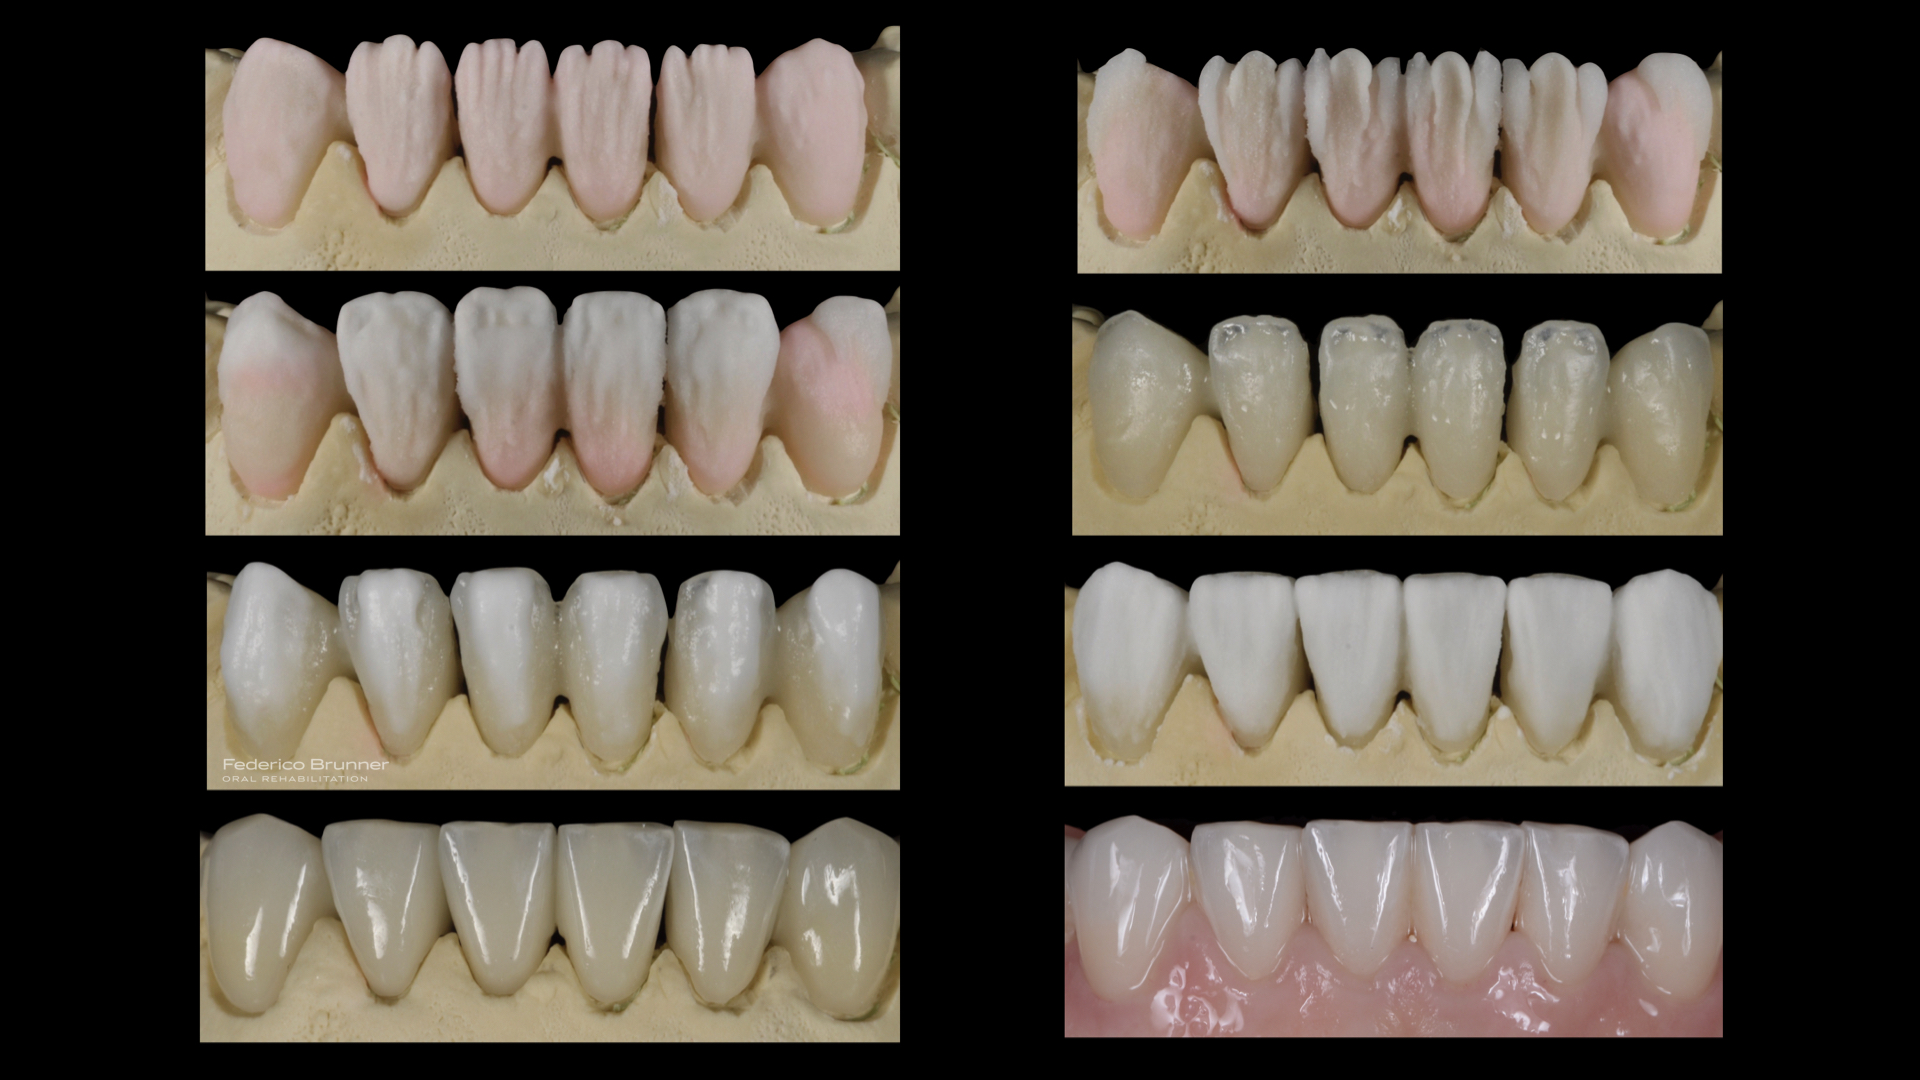

Una vez concluido el estudio de la sonrisa, creamos una simulación real o "mock-up" para que la paciente pudiera visualizar y comprender el resultado final antes de iniciar el tratamiento.

La paciente quedó encantada con el "mock-up", lo que nos permitió comenzar el tratamiento. En este proceso, realizamos un alargamiento coronario para mejorar la sonrisa gingival, ya que exponía demasiada encía. Luego, planificamos y ejecutamos una rehabilitación total cerámica adherida sin metal. Además, reemplazamos las piezas perdidas con implantes dentales, lo que nos permitió restaurar la función y hacer desaparecer los problemas masticatorios y digestivos.